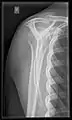

- Cervical spine: The standard projections in the UK AP and Lateral. Peg projection with trauma only. Obliques and Flexion and Extension on special request.[15] In the US, five or six projections are common; a Lateral, two 45 degree obliques, an AP axial (Cephalad), an AP "Open Mouth" for C1-C2, and Cervicothoracic Lateral (Swimmer's) to better visualize C7-T1 if necessary. Special projections include a Lateral with Flexion and Extension of the cervical spine, an Axial for C1-C2 (Fuchs or Judd method), and an AP Axial (Caudad) for articular pillars.